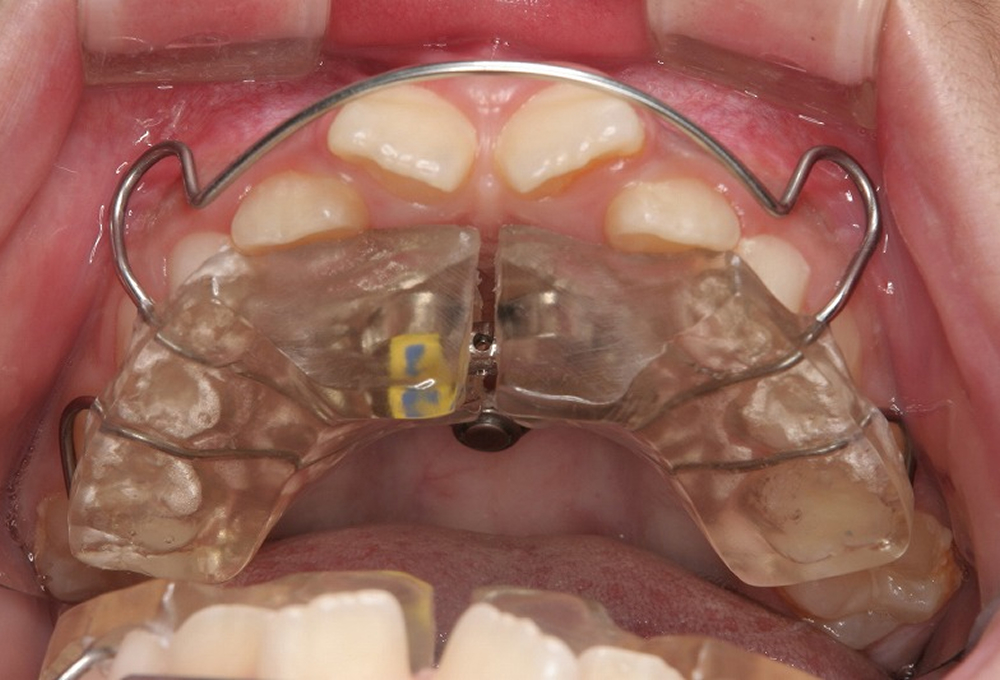

②拡大床(エキスパンジョンスクリュー 床矯正装置)を作製

③装着した所

④4ヵ月後 反対咬合が改善し、歯が並ぶスペースも確保できた。ここまできていれば永久歯列になったときの矯正は簡単です